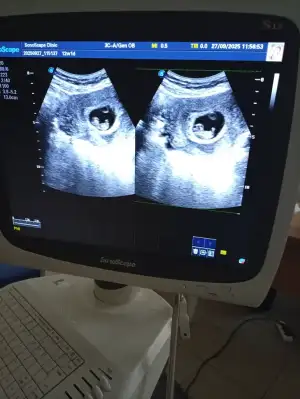

Merhaba banada yorum yapsanız 12 hafta karından çekildi